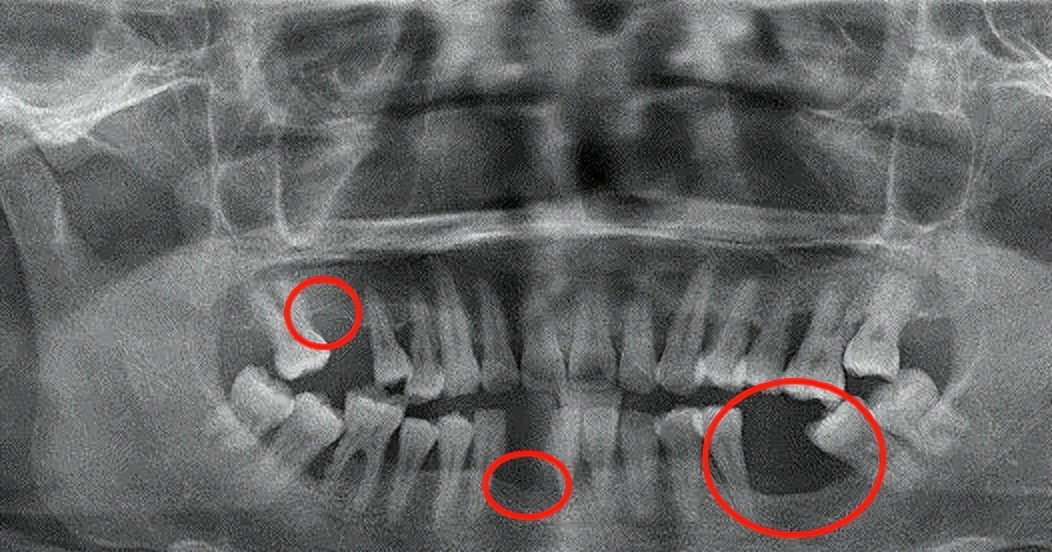

缺牙处牙槽骨被吸收、萎缩明显